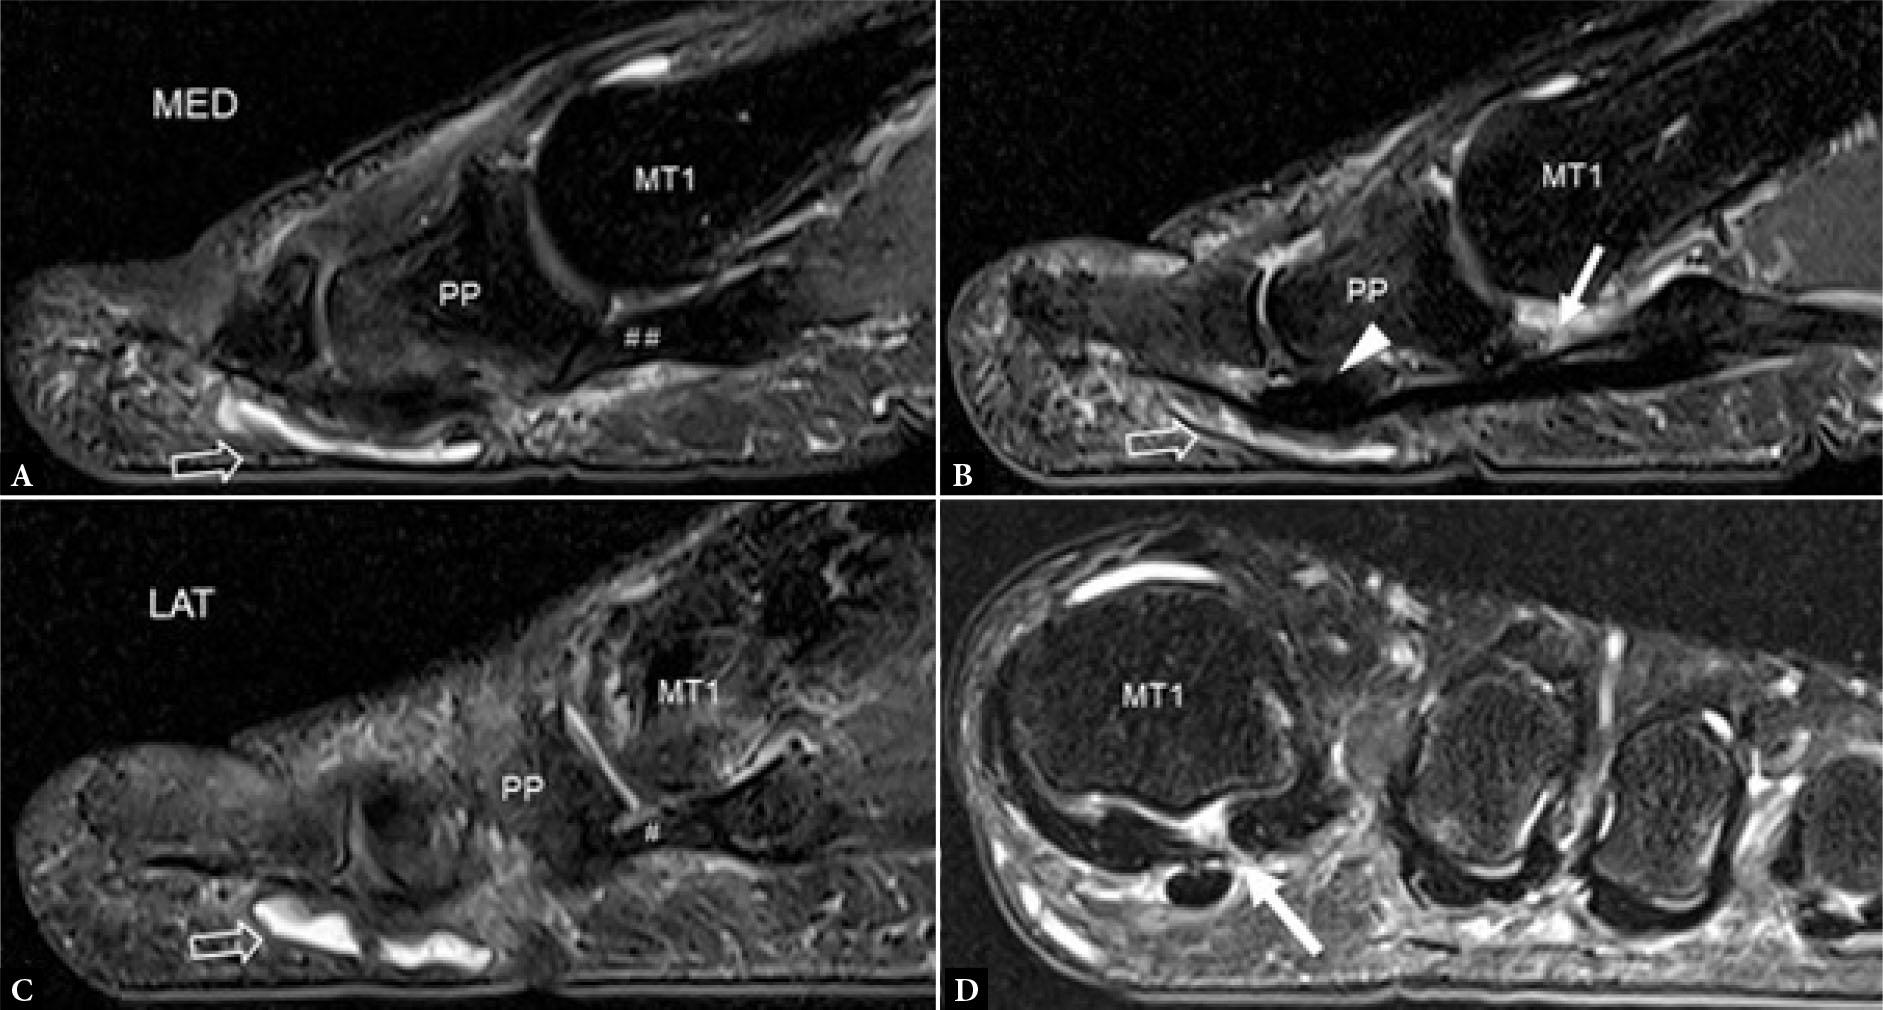

The plantar plate is the most frequently injured component of the 1st MTP joint though other supporting structures can also be torn either in isolation or in conjunction with a plantar plate tear. Plantar plate injury may be acute from traumatic hyperextension or chronic. The relative prevalence of acute or chronic tears seen is largely dependent on the referral population. Chronic tears occur in degenerative attenuated plantar plates from repetitive overload (Fig. 12). On MRI, degenerated plantar plates will tend to have intermediate rather than low signal intensity on all pulse sequences(11). Partial tears are more common than complete tears. If complete tears are accompanied by tearing of the supporting sesamoid ligaments, proximal migration of one or both sesamoid bones may occur. Unlike plantar plate tears of the lesser MTP joints, 1st MTP joint plantar plate tears tend not to induce exuberant reactive capsular/pericapsular fibrosis.

Fig. 12.

58-year-old female with forefoot pain. T2W fat-suppressed sagittal images though the A. medial, B. mid-line, and C. lateral aspects of the big toe. At the 1st MTP joint, the Index medial (##) and lateral (#) metatarso-sesamoid ligaments are intact with a complete tear of the attenuated plantar plate (arrow). At the interphalangeal joint, there is a degenerative thickened plantar plate (arrowhead) with an overlying mildly distended adventitial bursa (open arrow). D. T2W fat-suppressed coronal image also shows a tear of the inter-sesamoid ligament (arrow). MT1, 1st metatarsal bone, PP, proximal phalanx